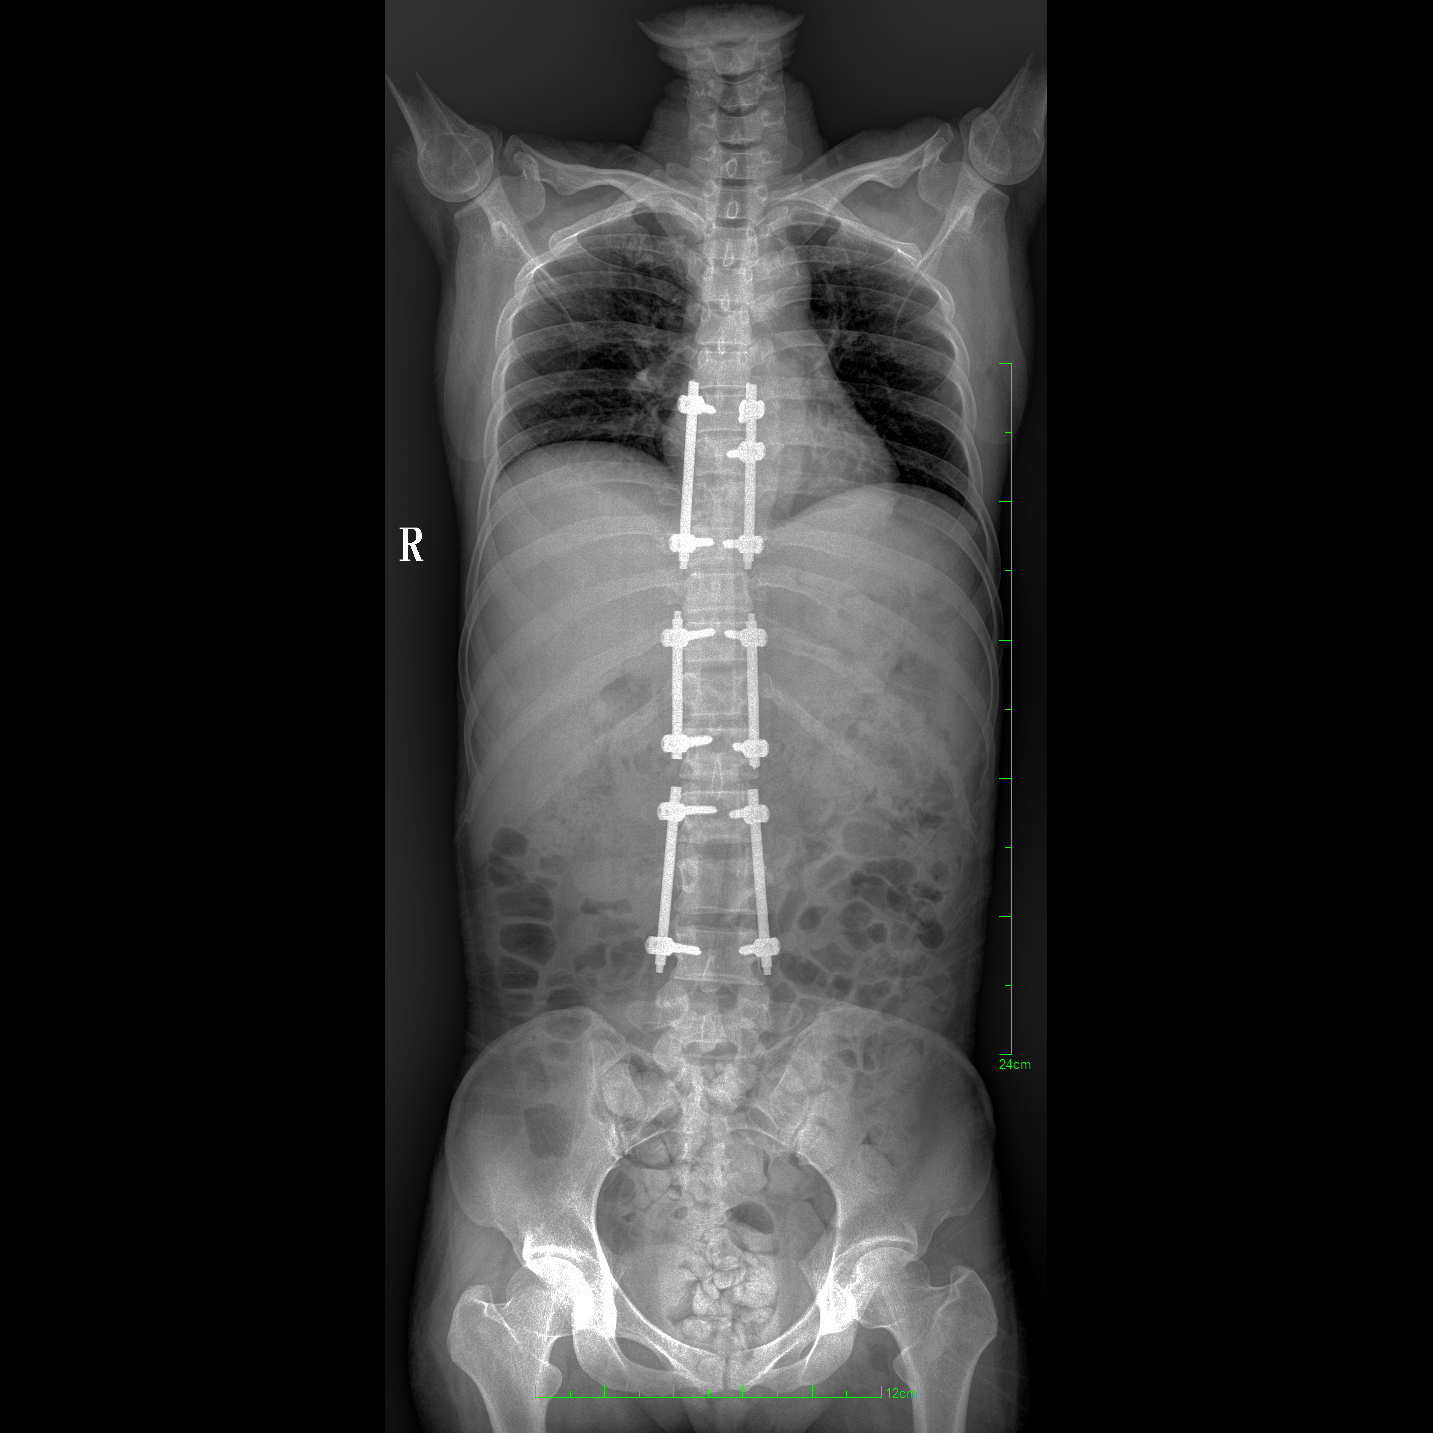

除常規(guī)靜態(tài)攝影外,PLX8600大平板具備動態(tài)透視和點片功能,透視采集功能可支持大視野、多角度的可視化觀察。通過可視化的動態(tài)影像,配合點片功能,能夠很好的觀察復(fù)雜部位病灶,有效的抓取關(guān)鍵幀,降低患者多次攝片的概率。如:全脊柱狀態(tài)評估、長骨關(guān)節(jié)活動度、下肢靜脈造影瓣膜功能評估、消化道功能評估、脊髓造影等更多大視野臨床應(yīng)用。